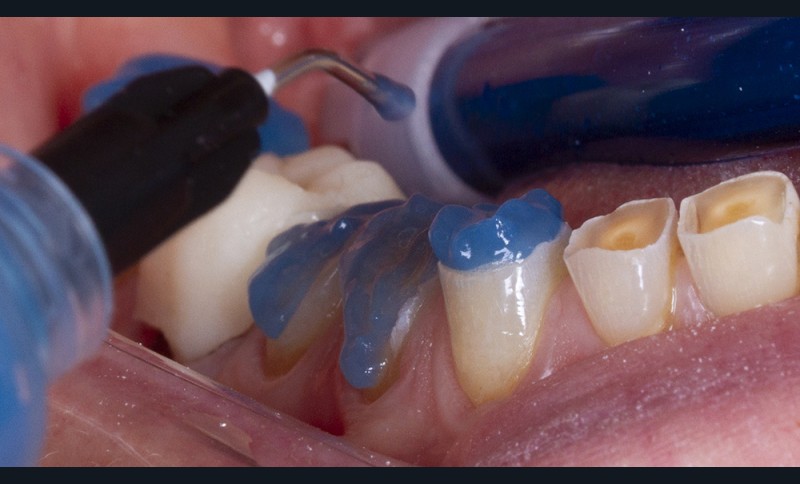

Un sablage à l’oxyde d’alumine est recommandé lorsque les usures sont marquées afin de préparer la surface de collage. Après rinçage, un mordançage à l’acide orthophosphorique est réalisé pendant 30 secondes sur l’émail et 15 secondes sur la dentine. Après un rinçage scrupuleux, un adhésif est étalé sur l’ensemble des surfaces mordancées, soufflé puis photopolymérisé (fig. 5).